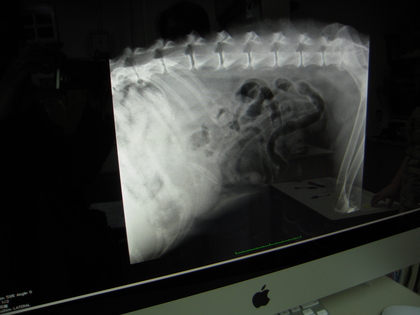

肝臓を確認するために撮った

レントゲン写真。

肝臓は大丈夫だったけど

胃の中に

飲み込んだであろう異物を発見!

いつ、なにを食べたのか。。。。

思い当たらないぞ。

無事に体のそとに

出てきますように。